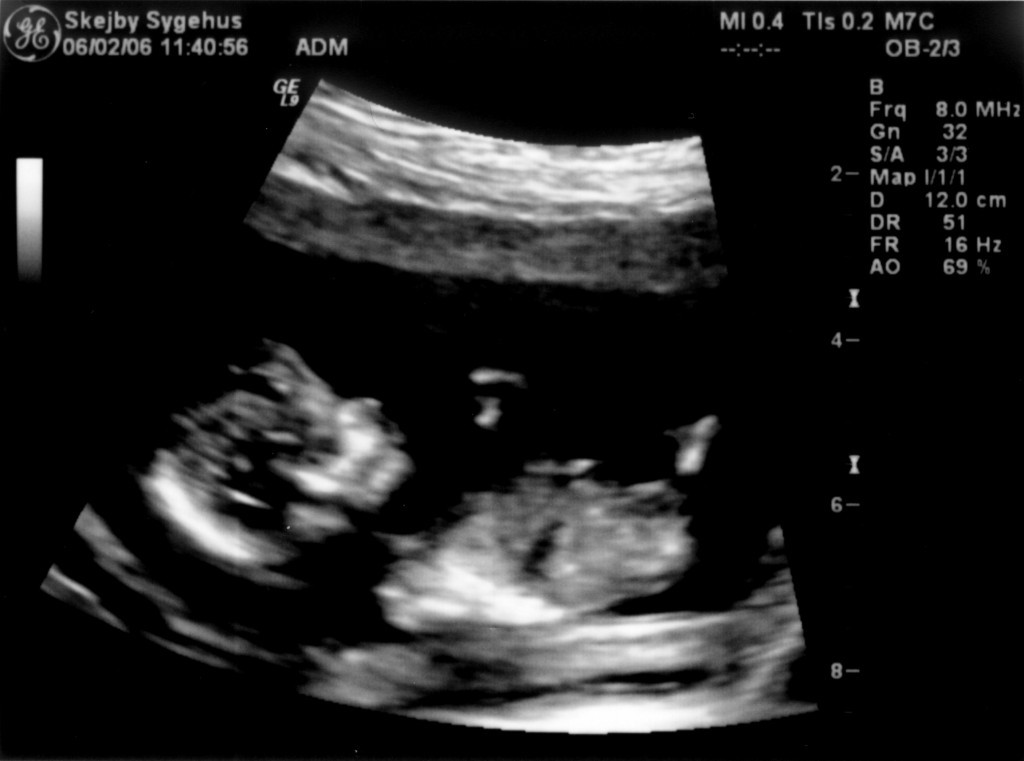

Ultralydsskanning den 22. marts 2006

Vi har så endelig været på Skejby Sygehus, hvor specialisterne skulle vurdere babys hjerte. Konklussionen var at baby og hendes hjerte ikke fejler noget - alt er i den skønneste orden. Der blev foretaget en meget grundig skanning og billederne blev vurderet af en afdelingslæge, en overlæge samt en overlæge med mange års international erfaring i børns hjertefejl. Det var en stor lettelse at hun ikke fejler noget. Baby blev undersøgt generelt en gang til at specialisterne og alt er som det skal være. De kunne desuden konstatere, at det er en pige... Du kan se de billeder vi fik fra skanningen herunder.

Baby ligger med hovedet nederst i midten og kigger op. Hun flekser så meget i ryggen at hendes ben går helt op over hovedet. Babys hjerte med nogle målinger.